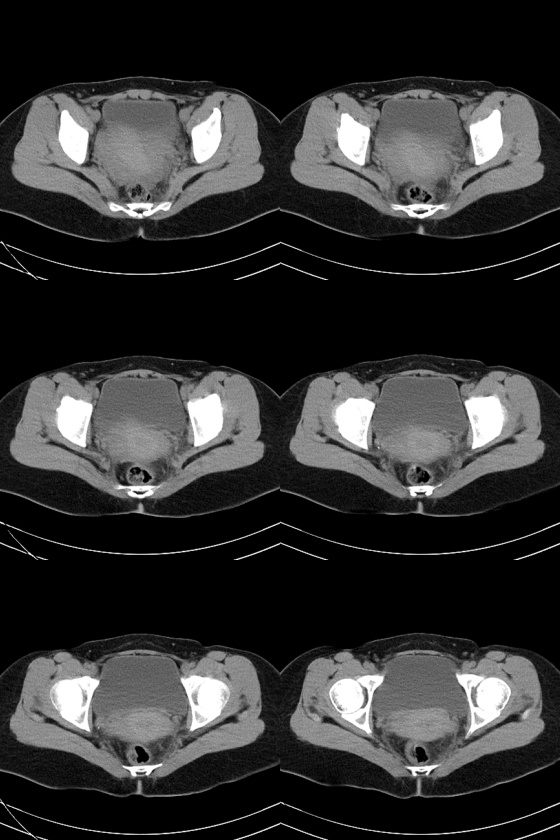

47岁女性,下腹部疼痛伴发热(38度)半月。b超提示宫底见3.0cm弱回声团块,边界清楚,形态规则,左侧附件区见不规则形态杂乱回声团块,其内可见液性暗区。b超同时提示肝脏见多个1.5cm的占位性病变。患者不同意做增强扫描。

1)左侧附件区囊实性占位性病变,性质待定;建议行进一步检查。2)子宫肌瘤?3)盆腔积液。

左侧附件区囊实性占位性病变,囊腺瘤或癌。

左侧附件区囊实性占位性病变,囊腺瘤或癌不排除!

左附件区囊性病变,囊内密度不均,也不能话是实性,也可以出血啊,所以还是做个增强或mri好点.不要作出太过重诊断.而且也没出见过肝ct图像.患者痛半月,可能囊肿伴出血或巧克力囊肿呢.

1、考虑左侧卵巢癌并肝转移(依据:左侧附件区囊实性包块,盆腔有积液,肝脏有多个占位),当然没有增强只是提示一种可能性。

2、病人有发烧,又不能排除左侧输卵管感染性病变,如病人不增强那就抗炎治疗后复查有助诊断。